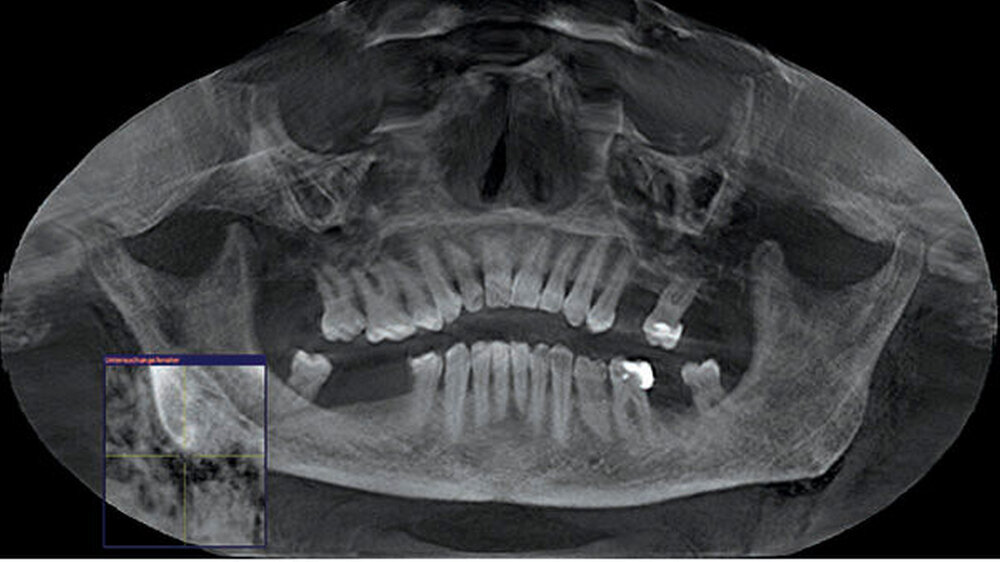

Zum Ausschluss einer Mittelgesichtsfraktur bei palpatorischem Weichteilemphysem erfolgte zur weiteren Diagnostik eine DVT-Aufnahme. Es zeigten sich keine Frakturen im Bereich des Mittelgesichts oder der Kiefer. Jedoch kam in der DVT-Bildgebung sowie der OPT-Optik ein massives Weichgewebeemphysem zur Darstellung (Abbildungen 2 bis 5).

Weiterhin wird deutlich, dass bei in aller Regel doch sehr eingeschränkter Beurteilbarkeit von Weichgewebe im DVT in diesem speziellen Fall eine weiterführende Diagnostik und Therapie eingeleitet werden konnte.

Das Emphysem war initial im DVT so eindrucksvoll sichtbar, dass es trotz fehlender klinischer Symptomatik im Thoraxbereich des Patienten, schwieriger Anamnese und blander zweidimensionaler Bildgebung der Lunge (RÖ-Thorax) der Faktor für eine weitere dreidimensionale Bildgebung (CT-Thorax) war, der letztendlich die Verdachtsdiagnose sicherte.

Zur Frakturdiagnostik im Mittelgesichtsbereich eignet sich das DVT sehr gut, außerdem ist die freie Luft des Emphysems im undifferenzierten Weichgewebe gut darstellbar.